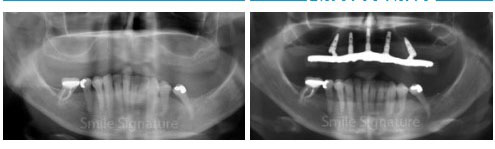

- Checking of Implants. On your return trip. We perform x-ray imaging to verify successful healing before taking precision impressions for your permanent set of dentures.

During your return visit, your dentist takes a panoramic x-ray to check if the implant posts is successfully integrated with the jaw bone. Your dentists takes tooth impressions to construct your permanent dentures in the dental labs. On its delivery, locators, balls or bars are screwed into the implant posts with the dentures snapped over securely over.

During your first visit, your dentist discuss and determines if that ProArch (All-on-4) concept is suited for your case. A panoramic x-ray and CT Scan is taken to confirm the treatment plan with you. Teeth impression is taken for a study model and prosthetic planning. If there are existing teeth, pre-planning is done to remove them and position the implant posts.

To determine the precise configuration for your smile, your dentist uses 3D CT scans and X-rays to map bone structure and recommend the specific implant-supported system that ensures long-term stability and comfort.